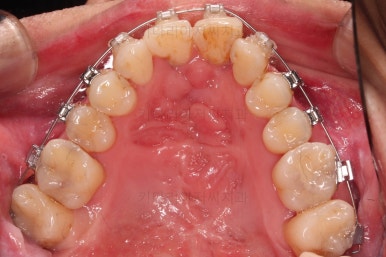

1. 초진 시 입안의 모습

부산구순구개열교정 키다리아저씨치과에 처음 내원하셨을 당시의 입안의 모습입니다.

이번 환자분도 이와 같은 일반적인 특징이 그대로 나타나 있었습니다.

양측성 구순구개열이었으므로 작은 앞니(대문니와 송곳니 사이)가 양쪽 다 결손이었고, 또 다른 이유로 아래 앞니도 1개 없는 상태였습니다.

위아래 장치를 부착했습니다.

초기 단계의 주안점은 아랫니와 악궁과 어울리는 윗니 악궁의 형태를 만들어 주는 것이고요.

악궁확장장치를 사용하지 않은만큼 철사의 형태를 잘 잡아가면서 악궁 형태를 개선시킵니다.